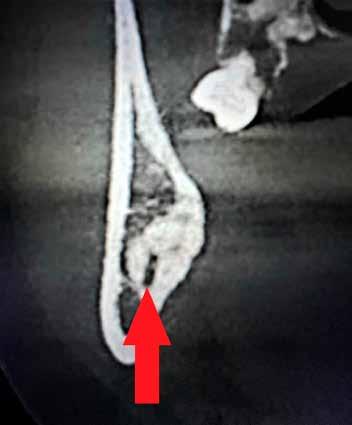

A CT metszetekben a 48-as gyökerei körbeölelik a canalis mandibularist, amelyet piros nyíllal jelöltünk a fotókon.

Szeretnék mutatni néhány ábrát az egyik bonyolult esetről, a közelmúltból. A CT-n látszik, hogy a három gyökér teljesen „körbenőtte” az ideget. Van olyan frontális metszeti kép, ahol csak a gyökerek vannak a nervus körül, ezen a szakaszon egyáltalán nincs meg a csontos fala a canalisnak. Szeparációs technikával, viszonylag könnyen, minimális traumával, szövődménymentesen sikerült eltávolítani a fog minden részét. A várakozásnak megfelelően, a beteg nem számolt be paraesthesiáról.